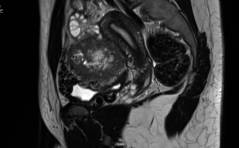

Der spezielle Fall: Perivaskulärer epitheloidzelliger Tumor (PECom)

Die 18-jährige Patientin meldete sich bei ihrer behandelnden Frauenärztin wegen rezidivierenden Bauchkrämpfen und allgemeinem Unwohlsein. Im Ultraschall zeigte sich eine grosse Raumforderung vor dem Uterus von 8 × 8 × 10 cm, im MRI konnte ein Sarkom nicht ... PDF Dokument